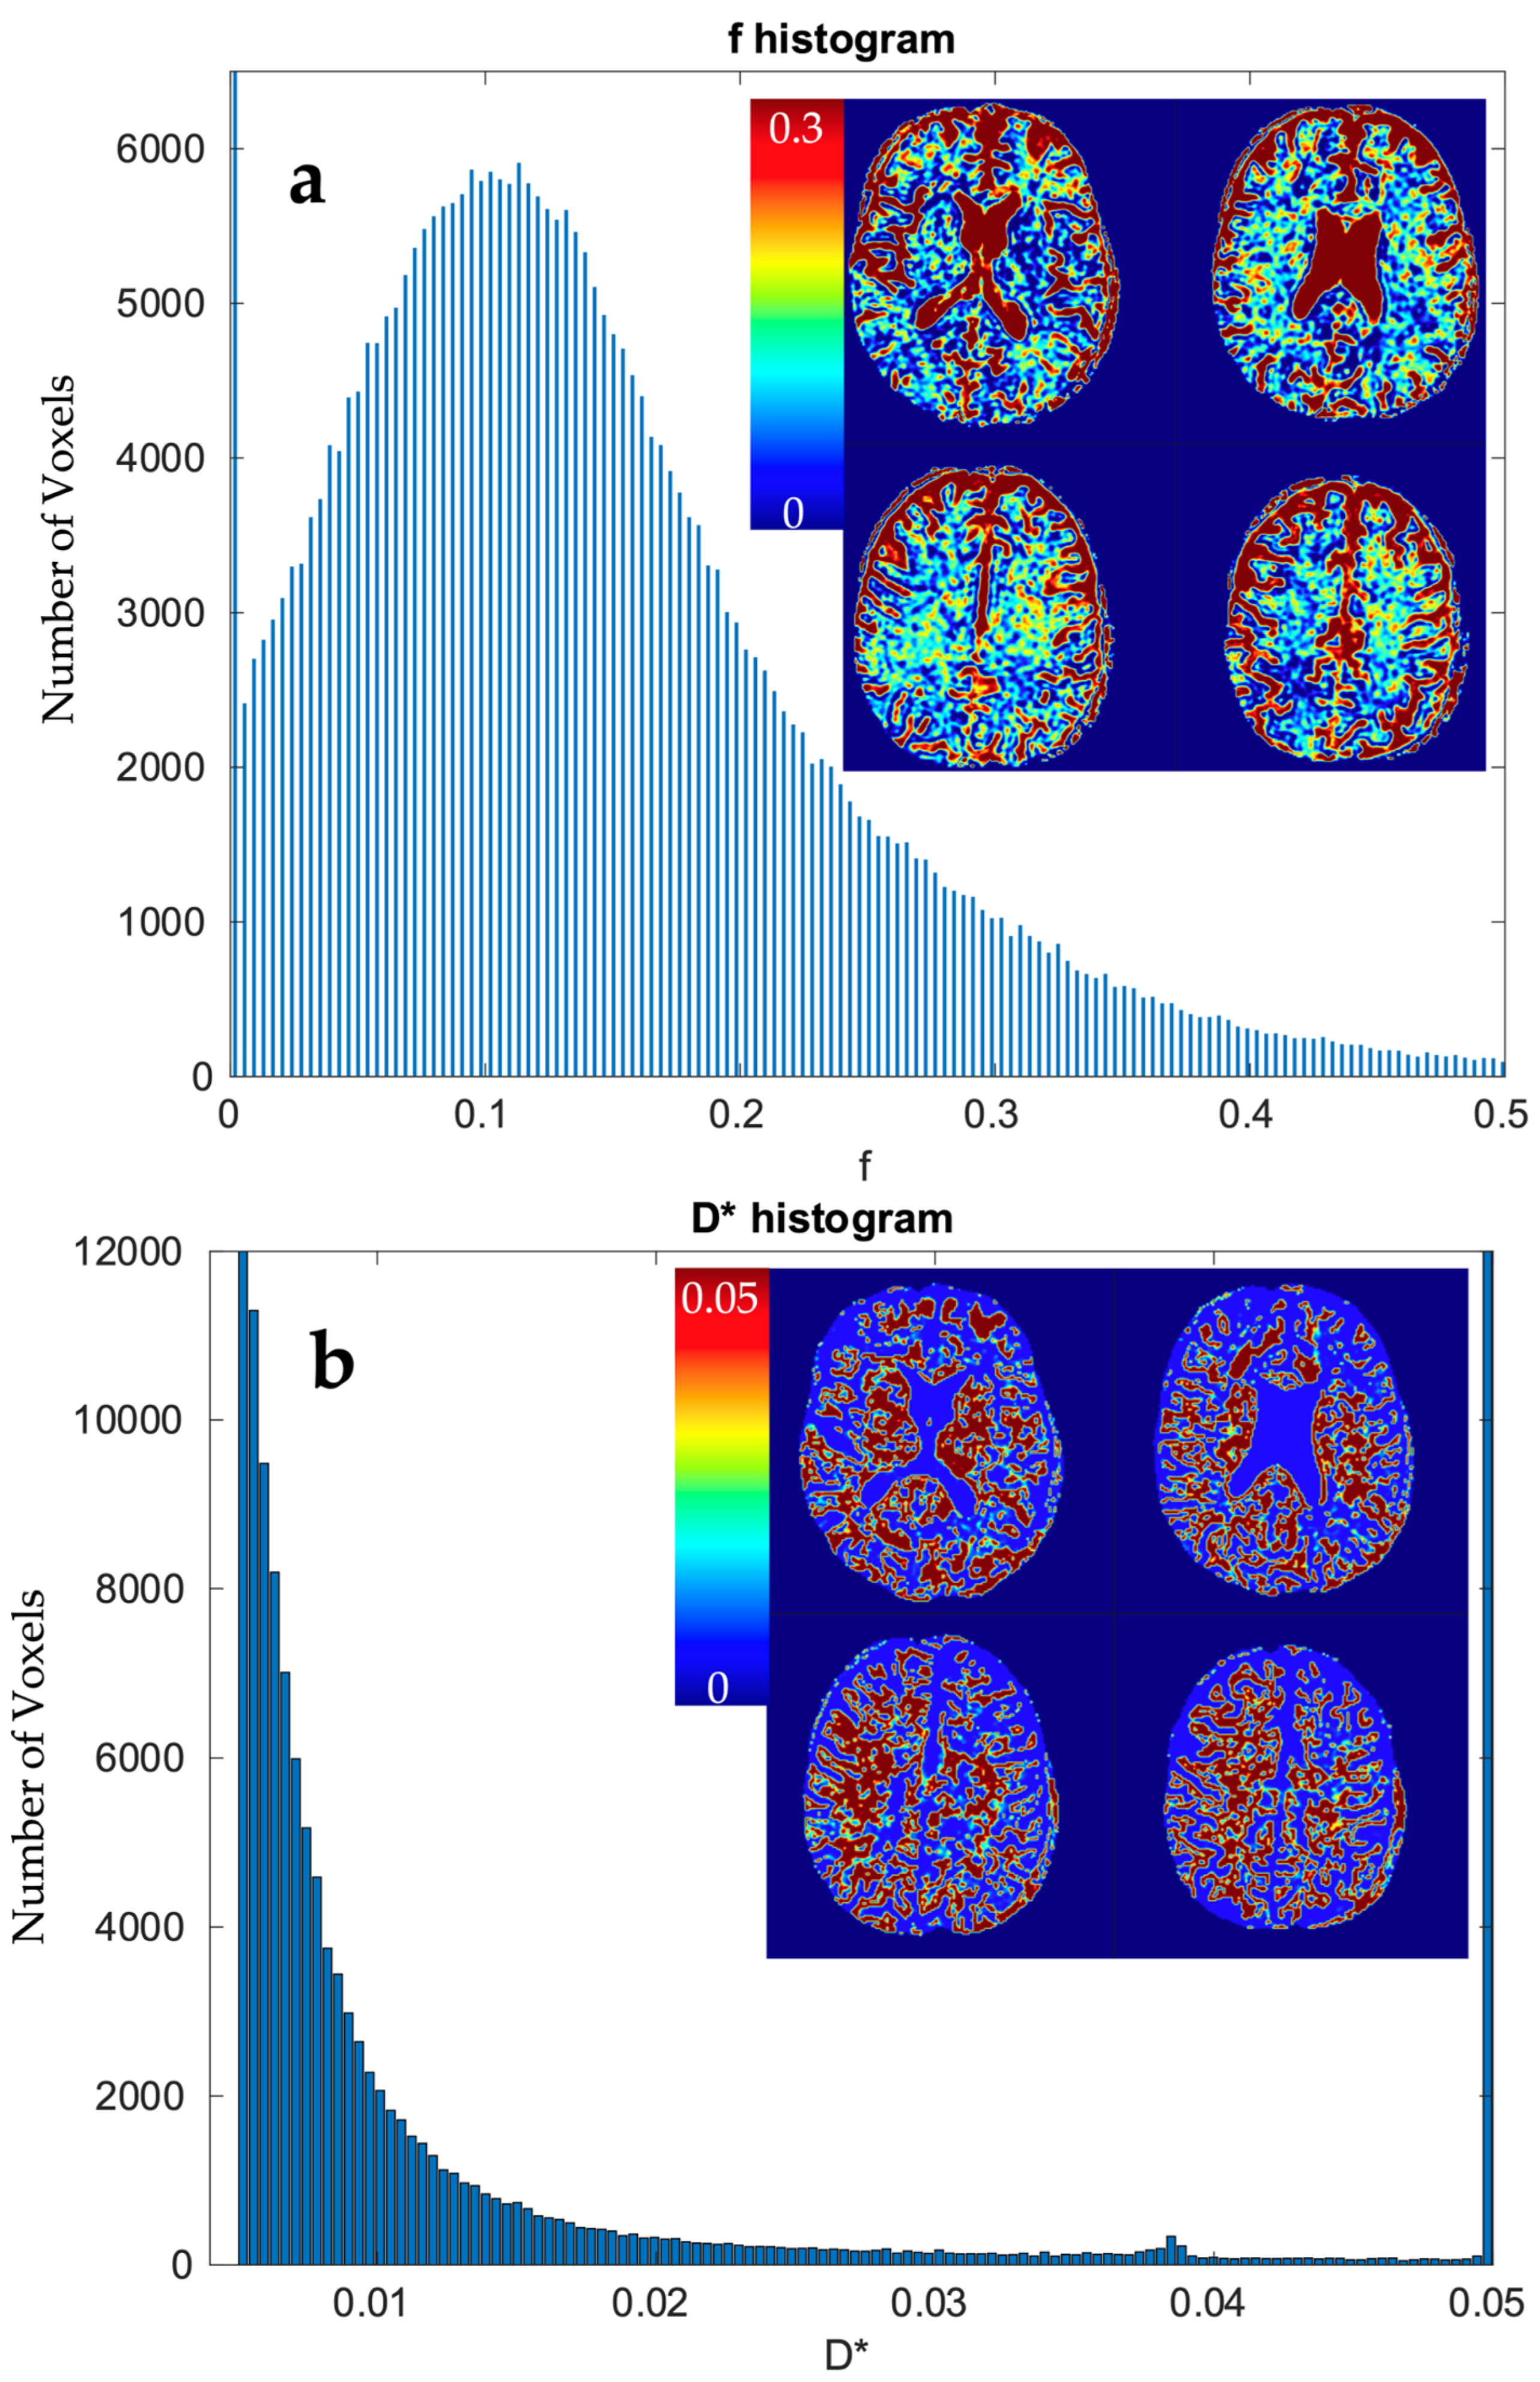

3.3.2. Calculation of IVIM Parameters